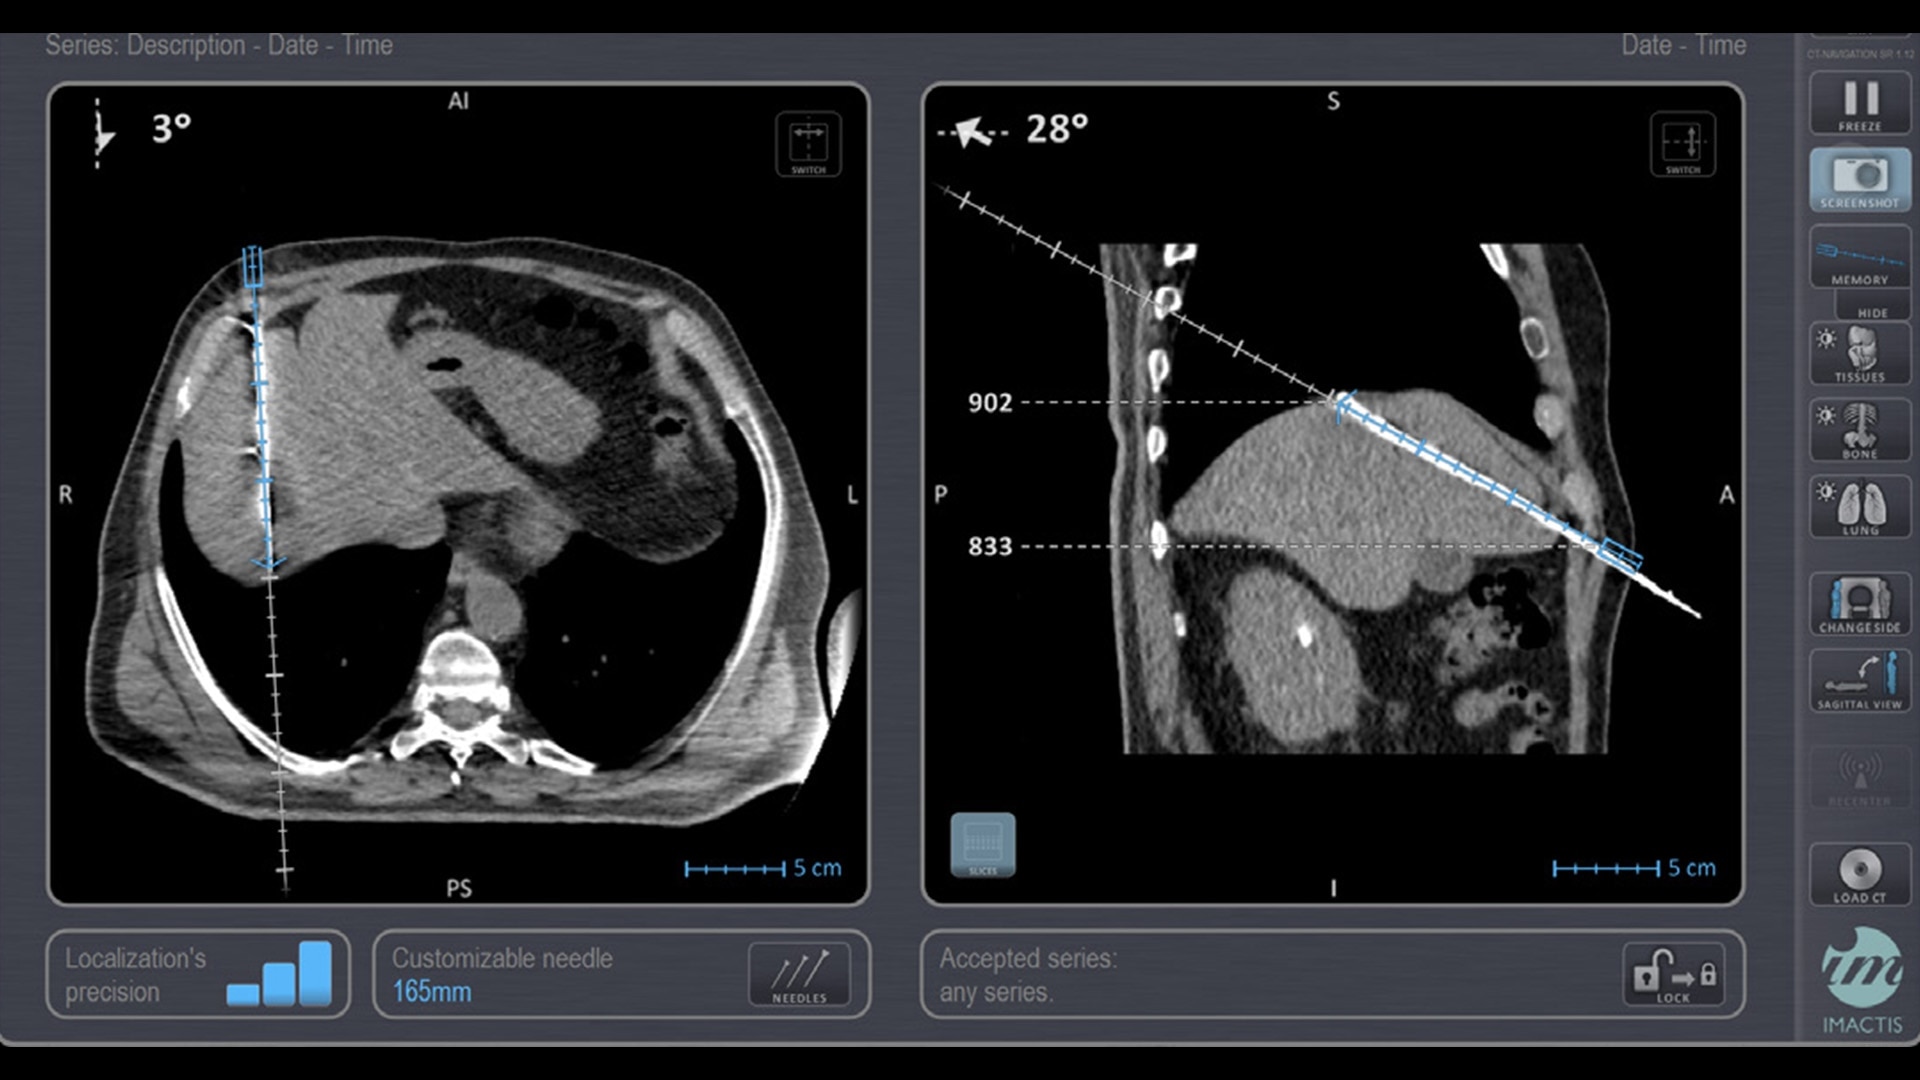

In interventional radiology, the success of the percutaneous procedure depends on correct needle positioning. The Imactis system helps the radiologist place one or more needles with great accuracy, in less time and with fewer control scans.

With real-time image reconstruction, live interactive navigation and no limit in angulation, the optimal clinical choices are clear.

Live 3D needle tracking, precise reproduction of your planned trajectory and continuous needle depth measurement help ensure optimal needle placement.